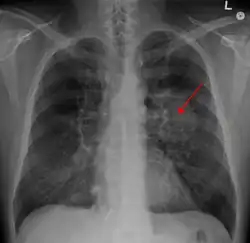

A chest X-ray showing a tumor in the lung (marked by arrow) | |

A person suspected of having lung cancer will have imaging tests done to evaluate the presence, extent, and location of tumors. First, many primary care providers perform a chest X-ray to look for a mass inside the lung.[9] The X-ray may reveal an obvious mass, the widening of the mediastinum (suggestive of spread to lymph nodes there), atelectasis (lung collapse), consolidation (pneumonia), or pleural effusion;[10] however, some lung tumors are not visible by X-ray.[6] Next, many undergo computed tomography (CT) scanning, which can reveal the sizes and locations of tumors.[9][11]